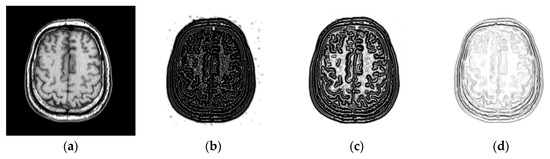

2.1. Structure of the Improved PCANet

2.1.1. The First Stage of PCANet

2.1.2. The Second Stage of PCANet

2.1.3. Output Stage

2.2. Structural Representation